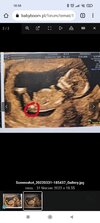

100% chlopak( usg)?Jak myslicie?

Kurka! Nie wiem dlaczego ale ja sobie ubzduralam tam siusiaka😆bo jakos na dziewczynke za dlugi ten wyrostek dla mnie 😁mam wrazenie, ze to hojnie obdarzony chlop. choc juz mam jednego syna🥰😍🥰i ddlatego dziewczynka rowniez bylaby mile widziana💖 tez wyczytalam, ze to ciutke za wczesnie...dlatego dziwie sie, ze lekarz podjal sie omreslenia plci juz na tym etapie. hmm... sama juz nie wiem🤔

Na tym etapie narządy chłopca i dziewczynki w zasadzie wyglądają niemal identycznie, więc na podstawie tego pierwszego zdjęcia nie mógł tego zrobić :)

Jeśli ta biała jaśniejsza kreseczka to wyrostek, to bardziej wskazywałoby to na dziewczynkę.

Ale ja nie jestem lekarzem, więc nie ma pewności czy ta kreseczka to wyrostek 😂

To masz na mysli co zaznaczylam w koleczku? Kurka nawet nie zauwazylam tego wczesniej i faktycznie tutaj " to cos" jest skierowane ku dolowi🤔dalas mi do myslenia

... Bo ja to bardziej szukalam czegos sterczacego lub plaskiego wzdlug kregoslupa...ale tutaj ewidentnie na kazdym zdjeciu jest chyba zasloniete nozkami... Ale kurcze faktycznie...ta biala struktura ( kreseczka o ktorej mowisz) jest konkretnie wyodrebniona i zwrocona ku dolowi. Teraz mam do myslenia😃. Powiem Ci, ze jestes bardzo spostrzegawcza. Choc ponoc ja do takowych naleze😃a kurna w ogole na to nie spojrzalam...a teraz jak powiedzialas to tylko to widze😆

Tak - to miałam na myśli. Ale czy to jest ten wyrostek płciowy, to nie mam pojęcia.

Na zdjęciach w necie nieco inaczej wygląda - bardziej cienka na linia jest.